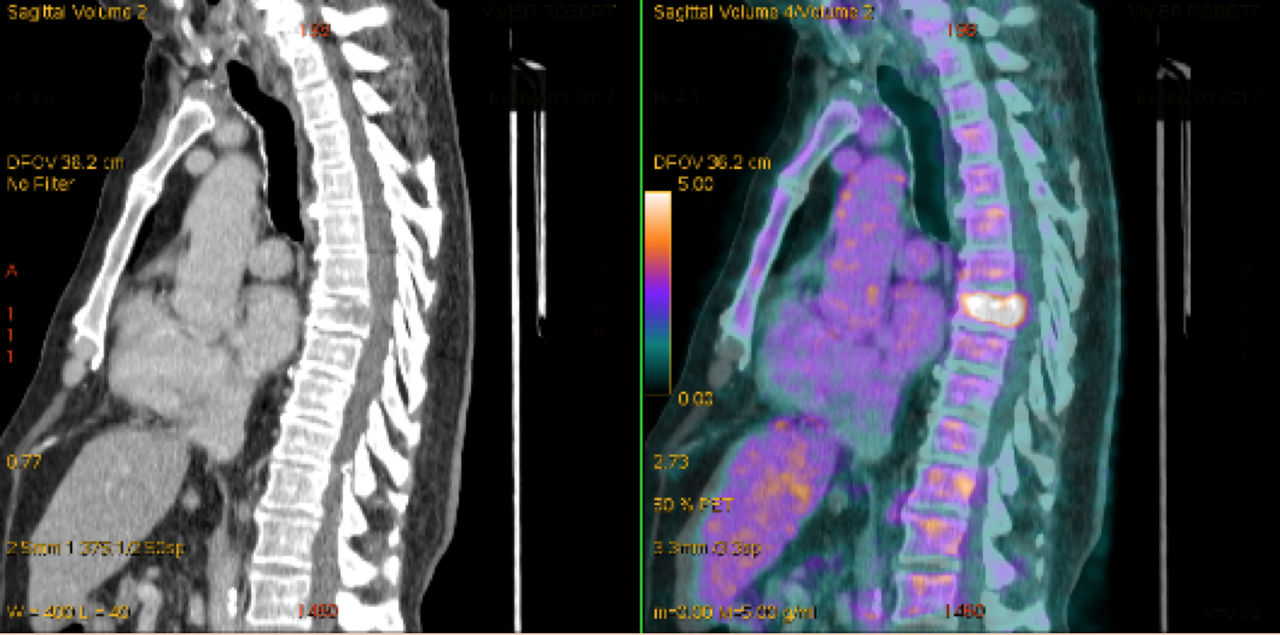

À propos de l’atteinte rachidienne vous examinez les clichés complémentaires suivants :

Question n°8 : Vous envisagez comme hypothèses diagnostiques

Hypothèse la plus probable dans un contexte de tumeur métastatique et devant l’unicité du tassement vertébral et l’aspect ostéolytique du les images du scanner

Le scanner thoraco-abdomino-pelvien retrouve un épaississement de la paroi vésicale de 15 mm, intéressant la face latérale gauche de la vessie, sans envahissement de la paroi rectale ni des organes de voisinage, ainsi que des adénopathies lombo-aortiques, iliaques internes, sus-claviculaires, et une ostéolyse de la vertèbre T8.